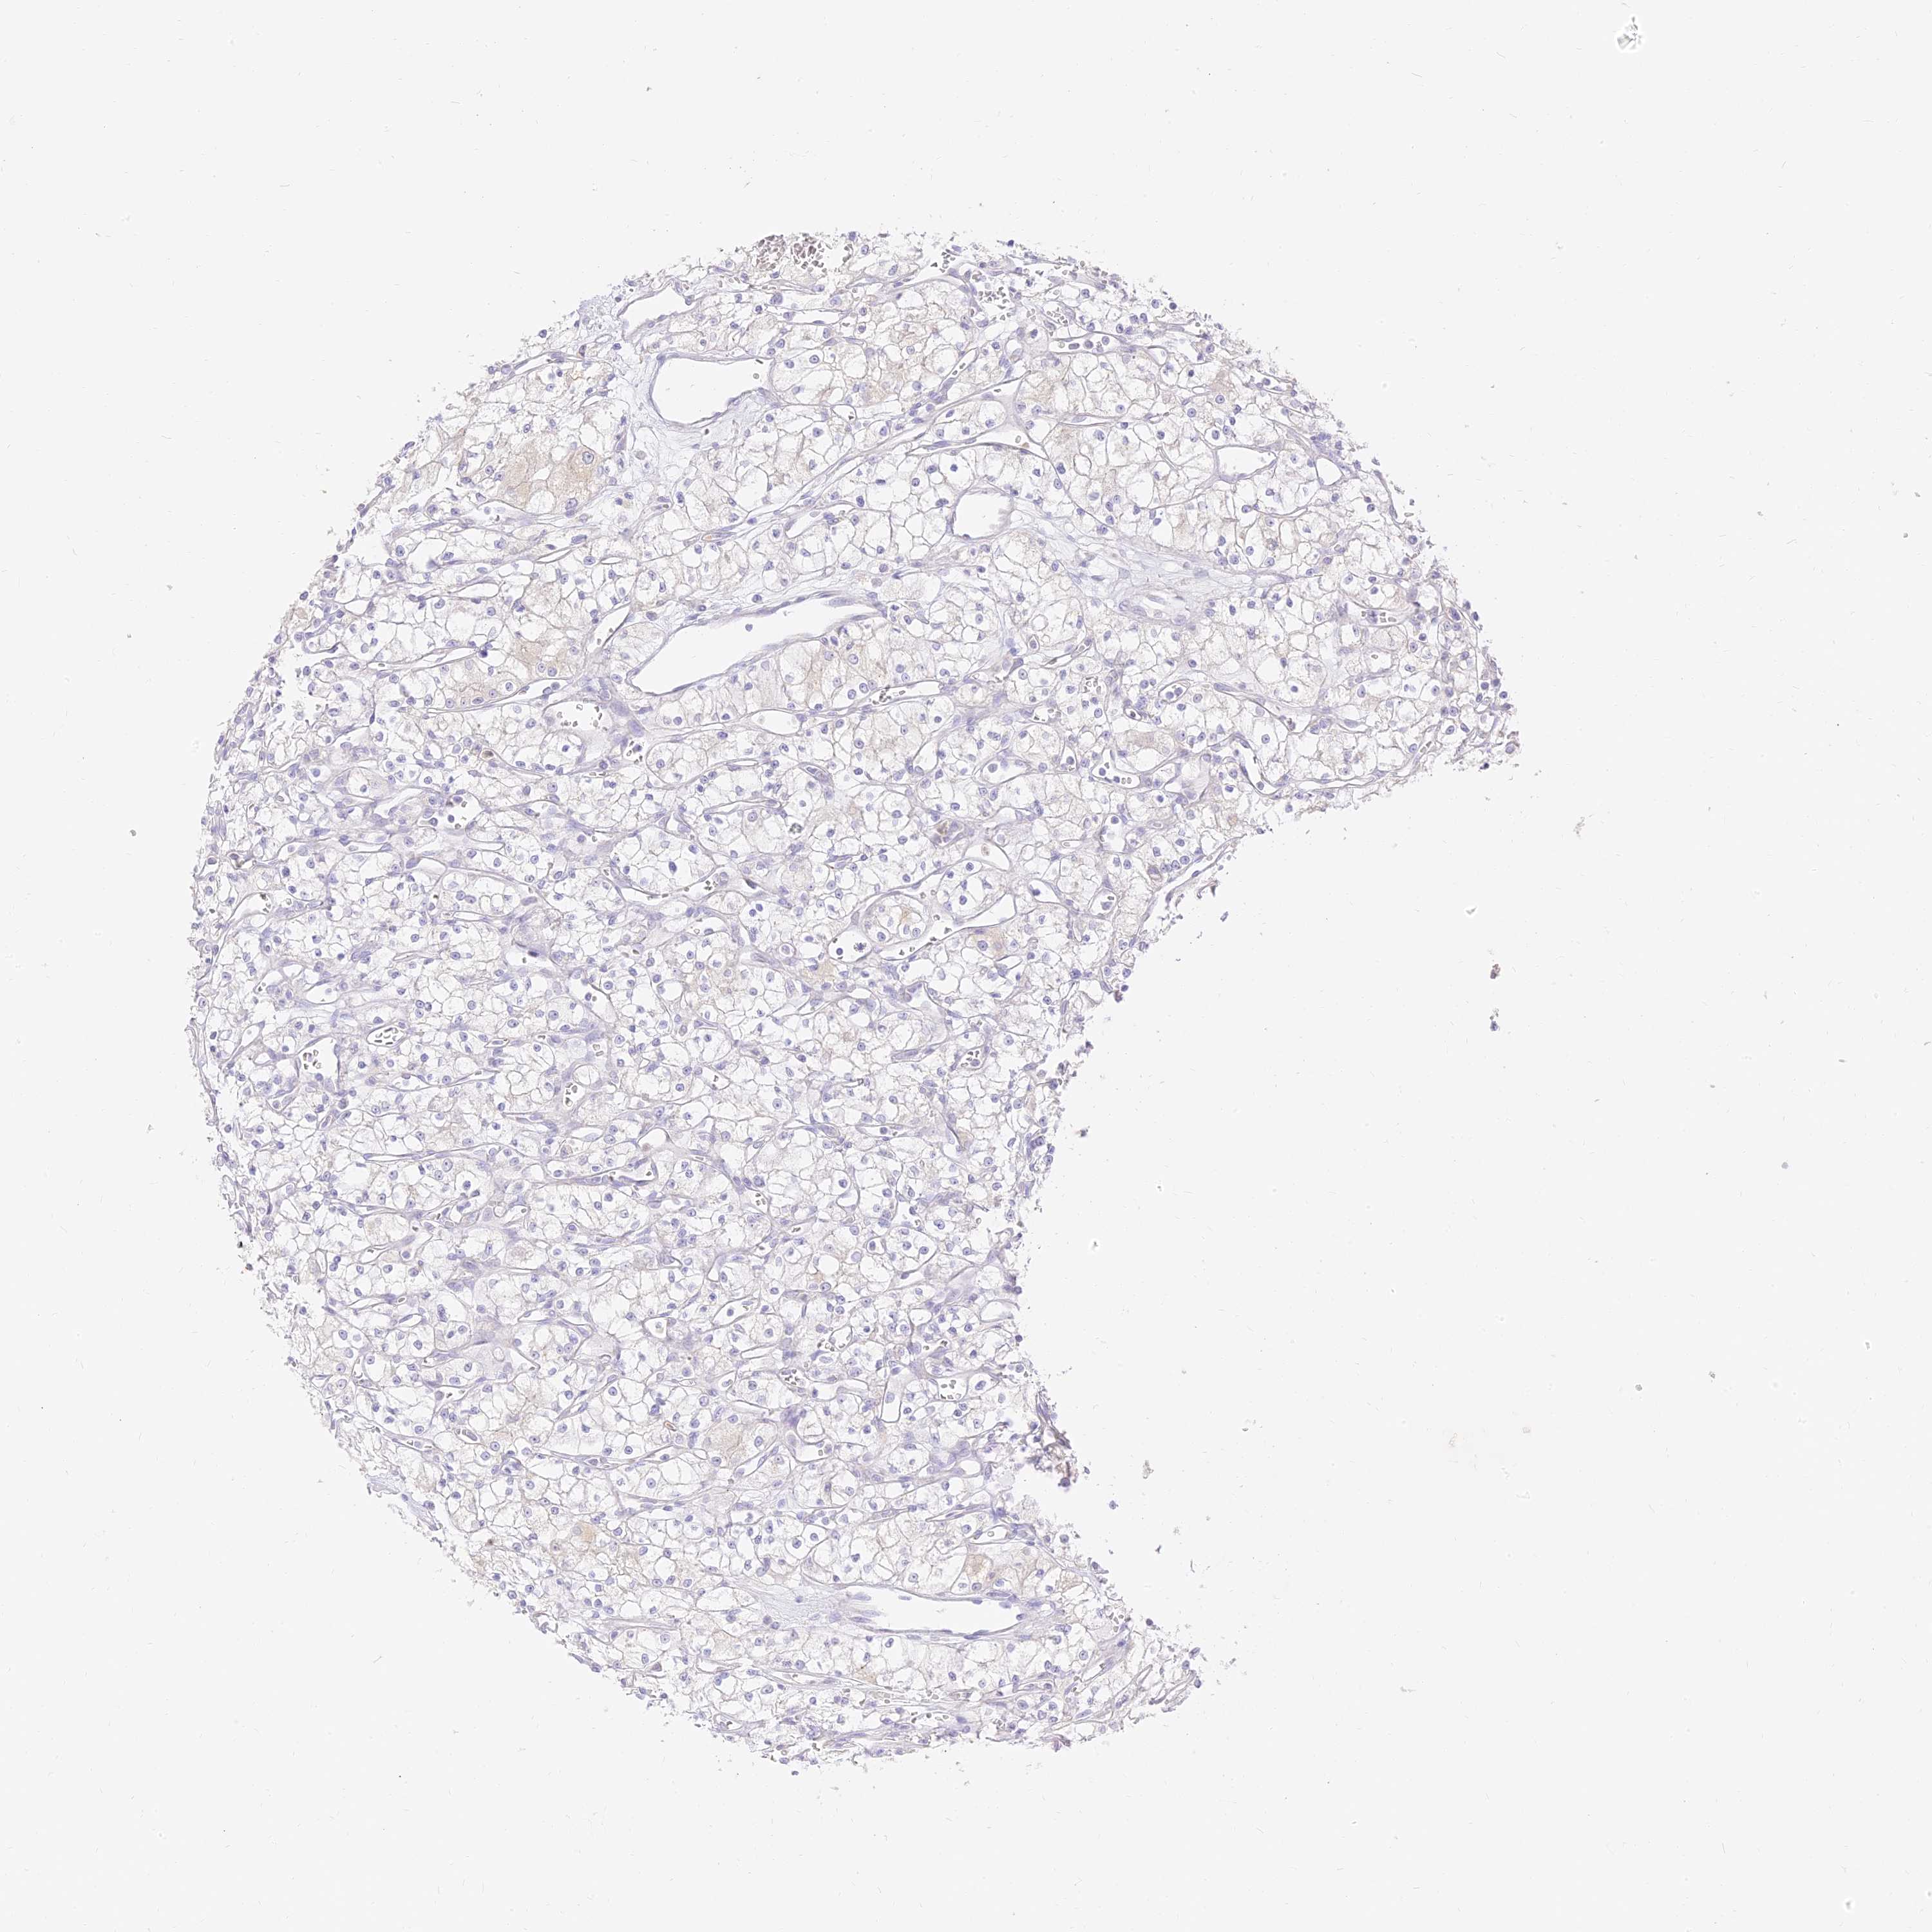

KIDNEY RENAL CLEAR CELL CARCINOMA (VALIDATION) - Interactive survival scatter ploti

The Survival Scatter plot shows the clinical status (i.e. dead or alive) for all individuals in the patient cohort, based on the same data that underlies the corresponding Kaplan-Meier plots. Patients that are alive at last time for follow-up are shown in blue and patients who have died during the study are shown in red.

The x-axis shows the expression levels (FPKM) of the investigated gene in the tumor tissue at the time of diagnosis. The y-axis shows the follow-up time after diagnosis (years). Both axes are complimented with kernel density curves demonstrating the data density over the axes. The top density plot shows the expression levels (FPKM) distribution among dead (red) and alive patients (blue). The right density plot shows the data density of the survived years of dead patients with high and low expression levels respectively, stratified using the cutoff indicated by the vertical dashed line through the Survival Scatter plot. This cutoff is automatically defined based on the FPKM cutoff that minimizes the p-score. The cutoff can be changed by dragging the vertical line or by entering a cutoff value in the square labeled "Current cut-off".

Under the Survival Scatter plot the p-score landscape (black curve; left axis) is shown together with dead median separation (red curve; right axis). Dead median separation is the difference in median mRNA expression between patients who have died with high and low expression, respectively. It is calculated as follows: median FPKM expression of dead patients with high expression - median FPKM expression of dead patients with low expression. This is intended to aid the user in visually exploring custom cutoffs and the associated p-scores and dead median separation.

Individual patient data is displayed and can be filtered by clicking on one or more of the category buttons on the top of the page. Categories describing expression level and patient information include: high, low, alive, dead, female, male and tumor stages. The scale of the x-axis can be toggled between linear and log-scale by clicking on the "x log" button. Mouse-over function shows TCGA ID, patient information and mRNA expression (FPKM) for each patient.

& Survival analysisi

Kaplan-Meier plots summarize results from analysis of correlation between mRNA expression level and patient survival. Patients were divided based on level of expression into one of the two groups "low" (under cut off) or "high" (over cut off). X-axis shows time for survival (years) and y-axis shows the probability of survival, where 1.0 corresponds to 100 percent.

SEC13 is not prognostic in Kidney Renal Clear Cell Carcinoma (validation)

Best expression cut offi

Based on the FPKM value of each gene, patients were classified into two groups and association between prognosis (survival) and gene expression (FPKM) was examined. The best expression cut-off refers the FPKM value that yields maximal difference with regard to survival between the two groups at the lowest log-rank P-value. Best expression cut-off was selected based on survival analysis .

When clicking on this number, the vertical dashed line indicating cut-off, the interactive survival plot, and the Kaplan-Meier curve will be adjusted to show results based on the best expression cut-off.

: 68.44

P scorei

Log-rank P value for Kaplan-Meier plot showing results from analysis of correlation between mRNA expression level and patient survival.

N/A

TCGA RNA samplesi

RNA-seq data is reported as average FPKM (number Fragments Per Kilobase of exon per Million reads), generated by the The Cancer Genome Atlas (TCGA) .

Normal distribution across the dataset is visualized with box plots, shown as median and 25th and 75th percentiles. Points are displayed as outliers if they are above or below 1.5 times the interquartile range. FPKM values of the individual samples are presented next to the box plot.

Average pTPM 58.7

Number of samples 100